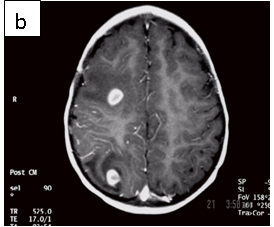

Figure 1: Neurocysticercosis in an 18-month child. a. Sagittal T1 without gadolinium; b. Axial T1 with gadolinium; c. Axial T2; d. Coronal FLAIR

Radiologic diagnosis: Neurocysticercosis.

| MRI | Live forms have a characteristic appearance: fluid-filled lesions containing an inverted scoleces, surrounded by thin low-signal capsule. They do not stimulate inflammation and do not enhance; dying forms do. In the less common racemose type, the cysts may be hard to see because they have similar imaging features as the CSF. |

For cysts that cause symptoms outside the CNS, surgical resection achieves cure. The treatment of symptomatic neurocysticercosis, which carries a 50% mortality rate, is more problematic. Two drugs, albendazole and praziquantel control symptoms and cause regression in the size and number of cysts in patients with viable (non-enhancing) cysts in their brain parenchyma. However, they provide limited improvement in patients with arachnoiditis and none in patients with intraventricular cysts. These latter patients should be treated with surgery or palliated with ventricular shunting, anticonvulsants, and anti-inflammatory drugs. According to our case’s physician, he did not receive anti-parasitic medication because the imaging features suggested that the parasites were dying (vasogenic edema and ring enhancement) (6).